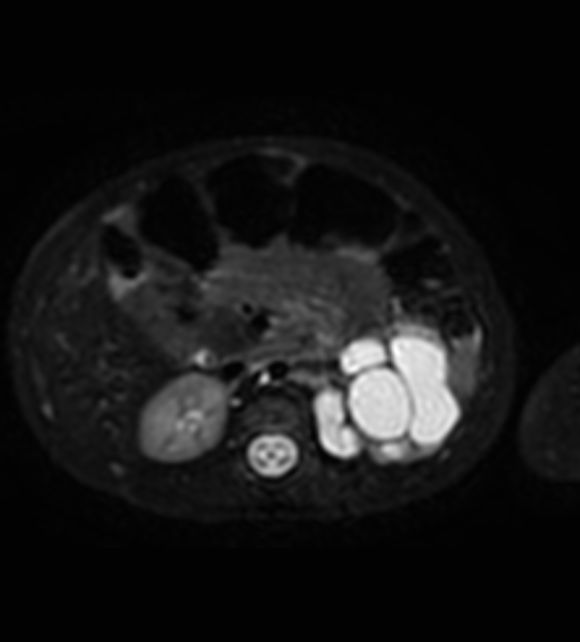

3D VIEW T2w SPIR - Axial reformat